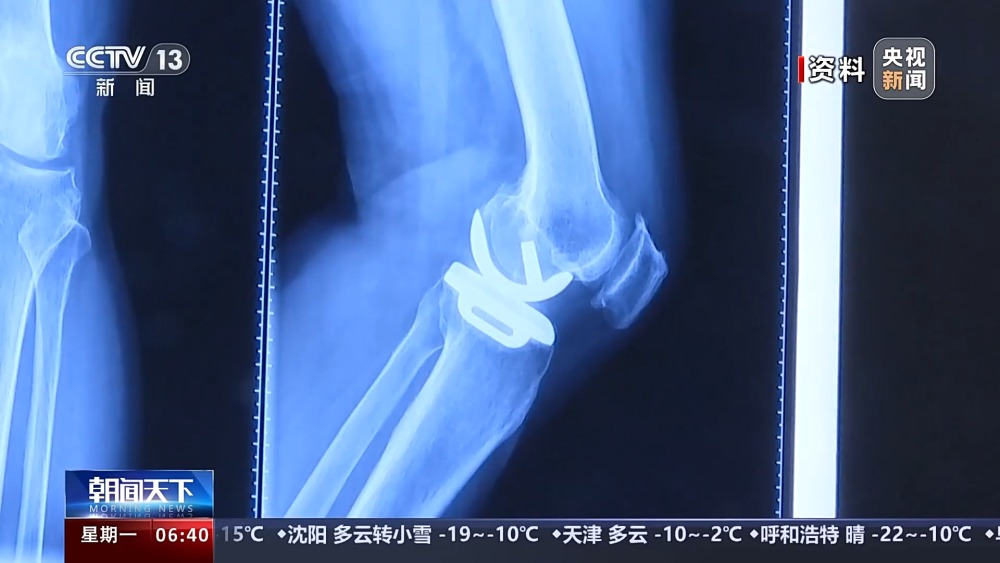

目前,我國有超過1億人患有骨關(guān)節(jié)炎,65歲以上人群中,骨關(guān)節(jié)炎發(fā)病率接近50%。以前,嚴(yán)重骨關(guān)節(jié)炎患者主要通過膝關(guān)節(jié)置換手術(shù)來維持行走等基本功能。膝關(guān)節(jié)置換手術(shù)存在術(shù)后關(guān)節(jié)僵硬、長期疼痛等問題。保膝治療包括藥物、理療等保守治療,以及手術(shù)治療。

保膝手術(shù)主要包括截骨術(shù)和單髁置換術(shù),其中截骨術(shù)在解決患者疼痛癥狀的同時(shí),阻止下肢異常應(yīng)力對膝關(guān)節(jié)的進(jìn)一步損傷,膝關(guān)節(jié)內(nèi)所有軟骨韌帶、半月板都得到了保留。內(nèi)側(cè)單髁置換術(shù),使膝關(guān)節(jié)外側(cè)健康的軟骨和半月板得到了保留,膝關(guān)節(jié)內(nèi)外側(cè)的韌帶維持原有狀態(tài),患者康復(fù)后,擁有正常的膝關(guān)節(jié)功能。